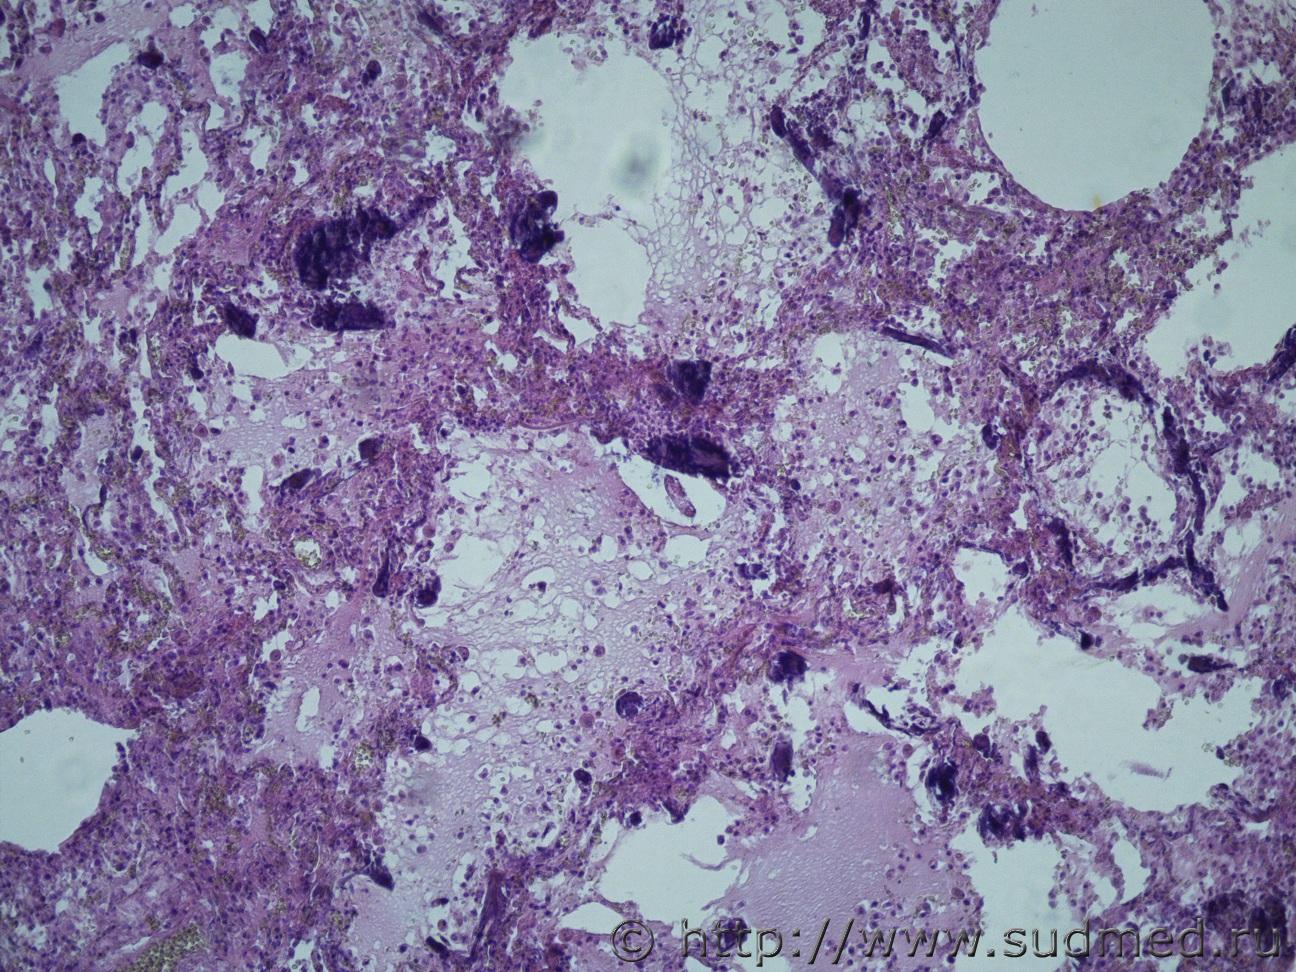

Ув. коллеги, нужна помощь, что это за заболевание легких? В атласе патологическая анатомия легких, нет не чего похожего. Это какое то диффузное паренхиматозное заболевание?. Жен 46 лет. Макро- Воздушность ткани верхних долей легких снижена, легочная ткань сиреневой окраски, образования диффузного характера беловато-сероватого цветы, плотные. По всем препаратам межальвеолярные перегородки инкрустированы известью. В просвете альвеол фибрин, лейкоциты, макрофаги.Судебная медицина - Прикрепленное изображение Судебная медицина - Прикрепленное изображениеСудебная медицина - Прикрепленное изображениеСудебная медицина - Прикрепленное изображениеСудебная медицина - Прикрепленное изображение

В просвете альвеол в основном мицелий грибов.

На втором фото похоже на ИФА (такие изменения могут быть и при РДС - ст.организации).

Петрификаты в межальвеолярных перегородках могут быть следствием их некроза ( в прошлом ).

Уважаемый Медик, как всегда в точку попадает. Это грибковая пневмония или пневмония , вызванная грибковой инфекцией рода Nocardia и возможно микст инфекция. Покрасить бы по Гимзе!